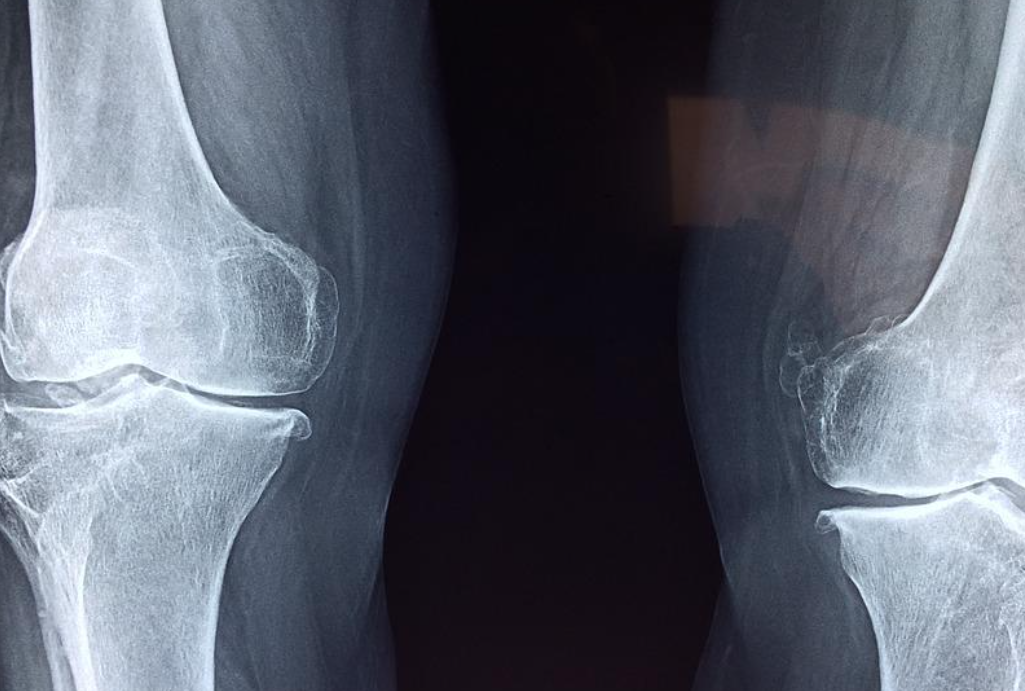

진단

골다공증은 골밀도를 측정하여 확인되는 T-값을 활용하여 진단합니다. 수치가 -1 이상이면 정상, -1에서 -2.5 사이이면 골감소증, -2.5 이하인 경우 골다공증으로 분류합니다.